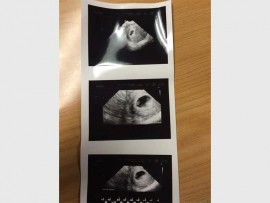

JUST two months after the passing of their premature baby, Hayley Meyer, Pieter (21) and Nicole (22) Meyer have been blessed with another miracle.

The couple announced on social media, on Thursday, June 30, that they are expecting again.

Nicole said she is between five to six weeks pregnant and this time she will visit her doctor more regularly. She is also drinking blood thinners and hormone pills to ensure a safe and healthy pregnancy.